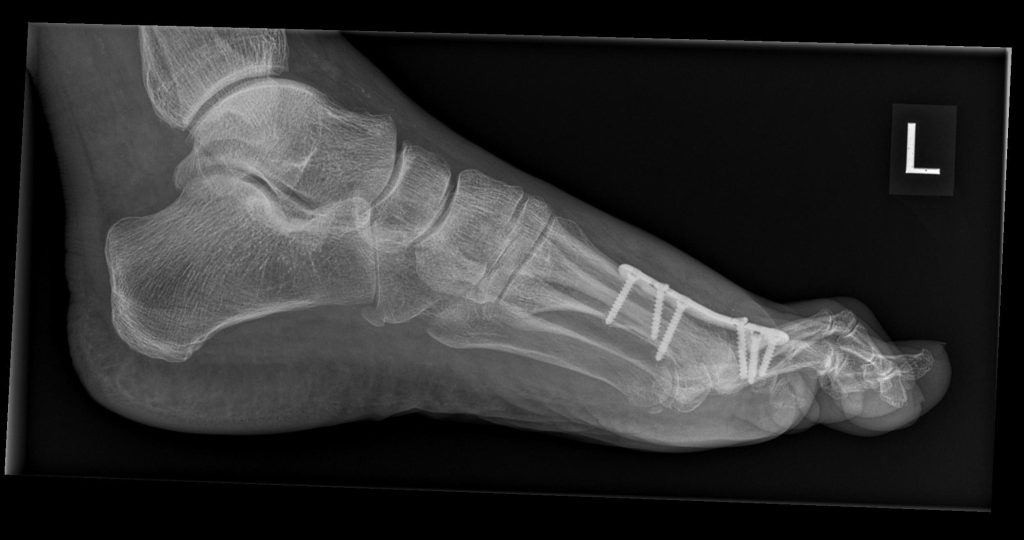

- Röntgen zur Beurteilung von Gelenkspalt, Osteophyten, Stellung

Operative Behandlung (Hallux-rigidus-OP)

Wenn Schmerzen trotz konservativer Maßnahmen anhalten oder die Alltagsbelastbarkeit deutlich eingeschränkt ist, besprechen wir mit Ihnen die OP-Optionen. Die Wahl richtet sich nach Stadium, Aktivität und persönlichen Zielen (z. B. Sport, Beruf, Schuhwerk).

| Arthrodese | schmerzfreies, stabiles Abrollen | Beweglichkeit im MTG I: Nein | sehr verlässliche Schmerzausschaltung, hohe Belastbarkeit | fortgeschrittene Arthrose/rigidus | Entlastung einige Wochen; Entlastungsschuh 6–8 Wo.; Sport schrittweise |

Arthrodese (Gelenkversteifung, fortgeschrittene Arthrose)

Versteifung des Großzehengrundgelenks in funktioneller Position. Sehr verlässliche Schmerzausschaltung auf Dauer, stabiles Abrollen, gute Belastbarkeit im Alltag und für viele Sportarten.